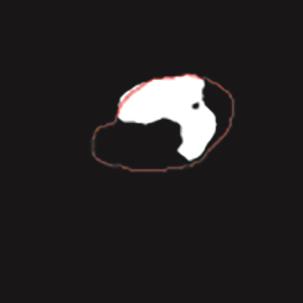

乳腺癌是全球女性最常见的恶性肿瘤之一,准确的病变分割对于乳腺癌的早期诊断与治疗具有重要意义。然而,由于病变形态的多样性以及超声成像机制的复杂性,现有基于深度学习的乳腺超声图像病变分割方法在分割准确性方面仍面临巨大挑战。为进一步提升乳腺超声图像中病变区域的分割精度,该文基于经典U-Net架构,提出了一种新型乳腺超声图像病变分割网络(CWSASKM-BBAM-Net)。首先,在网络中引入逐通道空间自适应选择核卷积模块(CWSASKM),根据不同通道的语义特征为每个空间位置自适应选择感受野大小,以增强多尺度信息的建模能力;然后,引入双向边界感知机制(BBAM),通过融合正向与反向注意力,对目标显著区域及其边界进行协同建模,同时逐步提升对非显著区域与病变区域的区分能力,以进一步强化边界信息的表达;最后,在3组公开乳腺超声图像数据集(BUSI、UDIAT和STU)上开展分割实验。结果表明:该方法在数据集BUSI上的杰卡德指数、精确率、召回率和Dice相似系数分别为71.97%、82.85%、81.40%和80.44%,较次优方法分别提升1.69、1.05、1.28和1.84个百分点;在数据集UDIAT上,这4项指标分别达到78.14%、88.31%、86.73%和86.10%,较次优方法分别提升了2.75、2.04、0.56和2.01个百分点;在外部数据集STU上,该方法也取得了优于其他方法的整体表现。实验结果表明,CWSASKM-BBAM-Net在乳腺超声图像分割任务中展现出更优的整体性能。